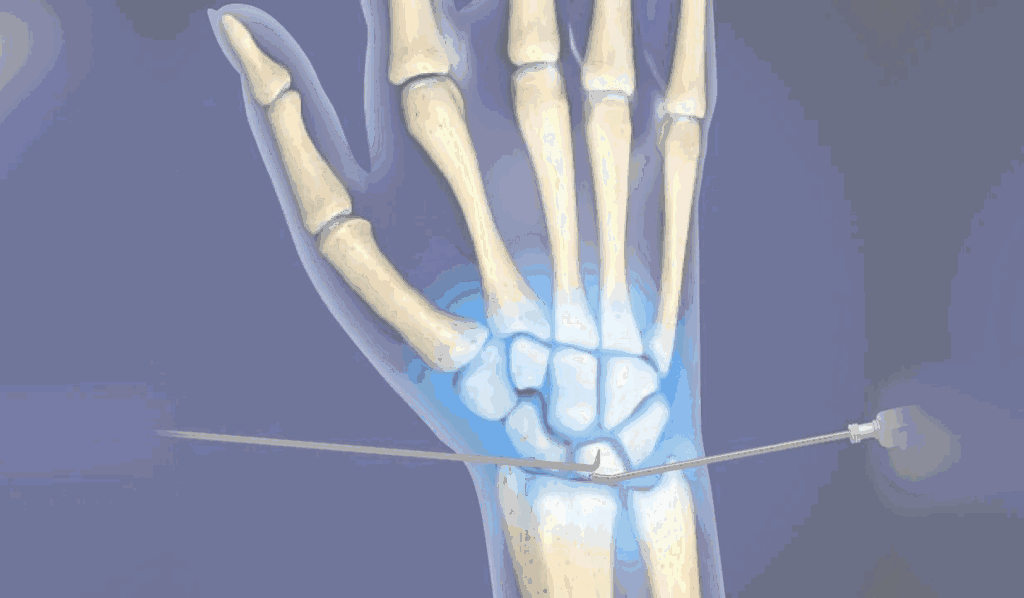

The young, male patient had the fracture of Rt scaphoid/ due to falling on an outstretched hand. The scaphoid fracture was treated, with the plaster cast for 1 ½ month elsewhere. Fracture of Rt Scaphoid was not united. This condition is called, the scaphoid non-union. It was treated with open reduction, and the iliac crest, bone grafting, and K wire stabilization.

During Surgery